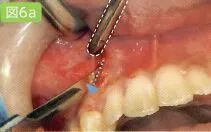

吸引针刺部位溢出的麻醉药物

虚线部分为吸唾管